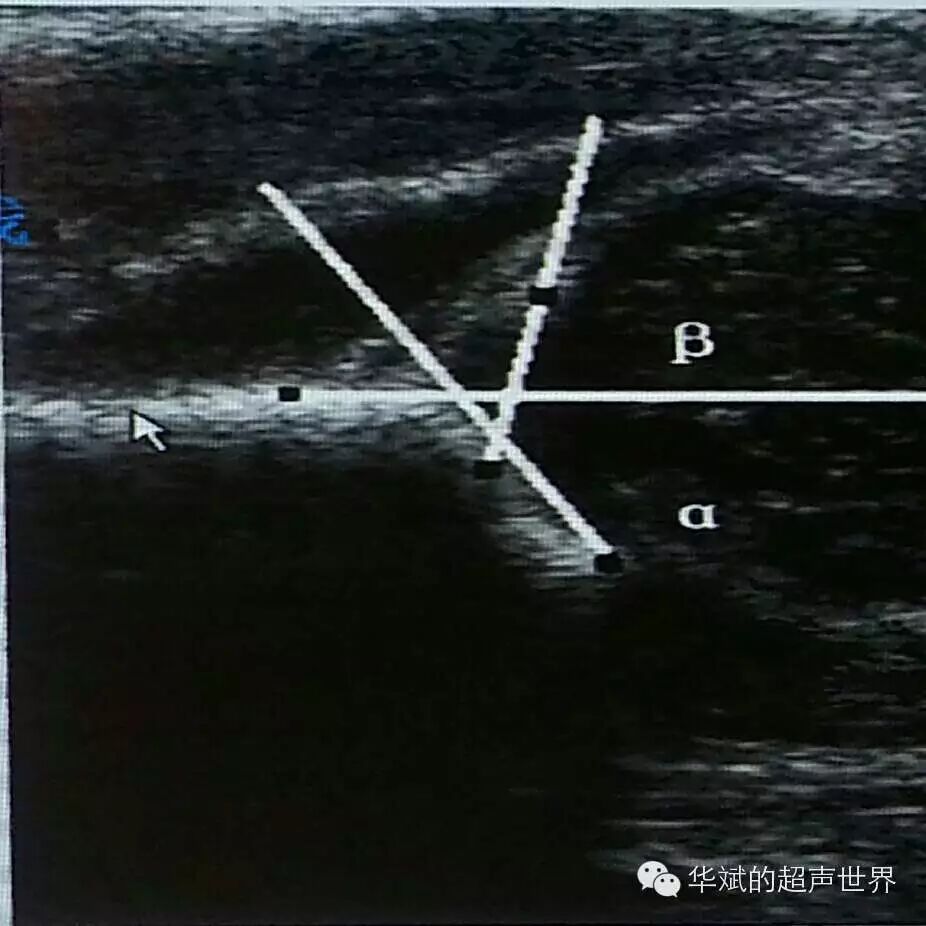

但是,对于未成熟髋关节的测量颇多争议(图4)。α角的测量没有争议,都认为骨性髋臼顶线是由图中的软骨性髋臼顶与骨性髋臼顶的分界点(图4中1点处)与3点之间的连线。按照Graf本人的主张,唇线应该是图4中1点处与2点之间的连线。但是这样测量的结果会把导致β角测值严重畸大,结果使得很多仅仅是未成熟的髋臼被误判为异常髋臼,假阳性率极高。为了减低假阳性率,因此很多研究者不赞同Graf本人关于未成熟髋的唇线测量方法,而采用髋顶线与髂骨线的交点(图4中的4点处)到唇缘(2点处)的连线为唇线。

图4 未成熟髋关节的不同测量方法

图5 Graf主张的未成熟髋的α角与β角的测量。

正是因为关于唇线的画法存在差异,造成不同研究者关于β角的意义的差异很大,因此很多指南中索性摒弃了β角,而只推荐测量α角作为髋臼分型的依据。我们工作中也是以α角为主要参考,并结合动态检查做出判断,β角一般可以忽略。